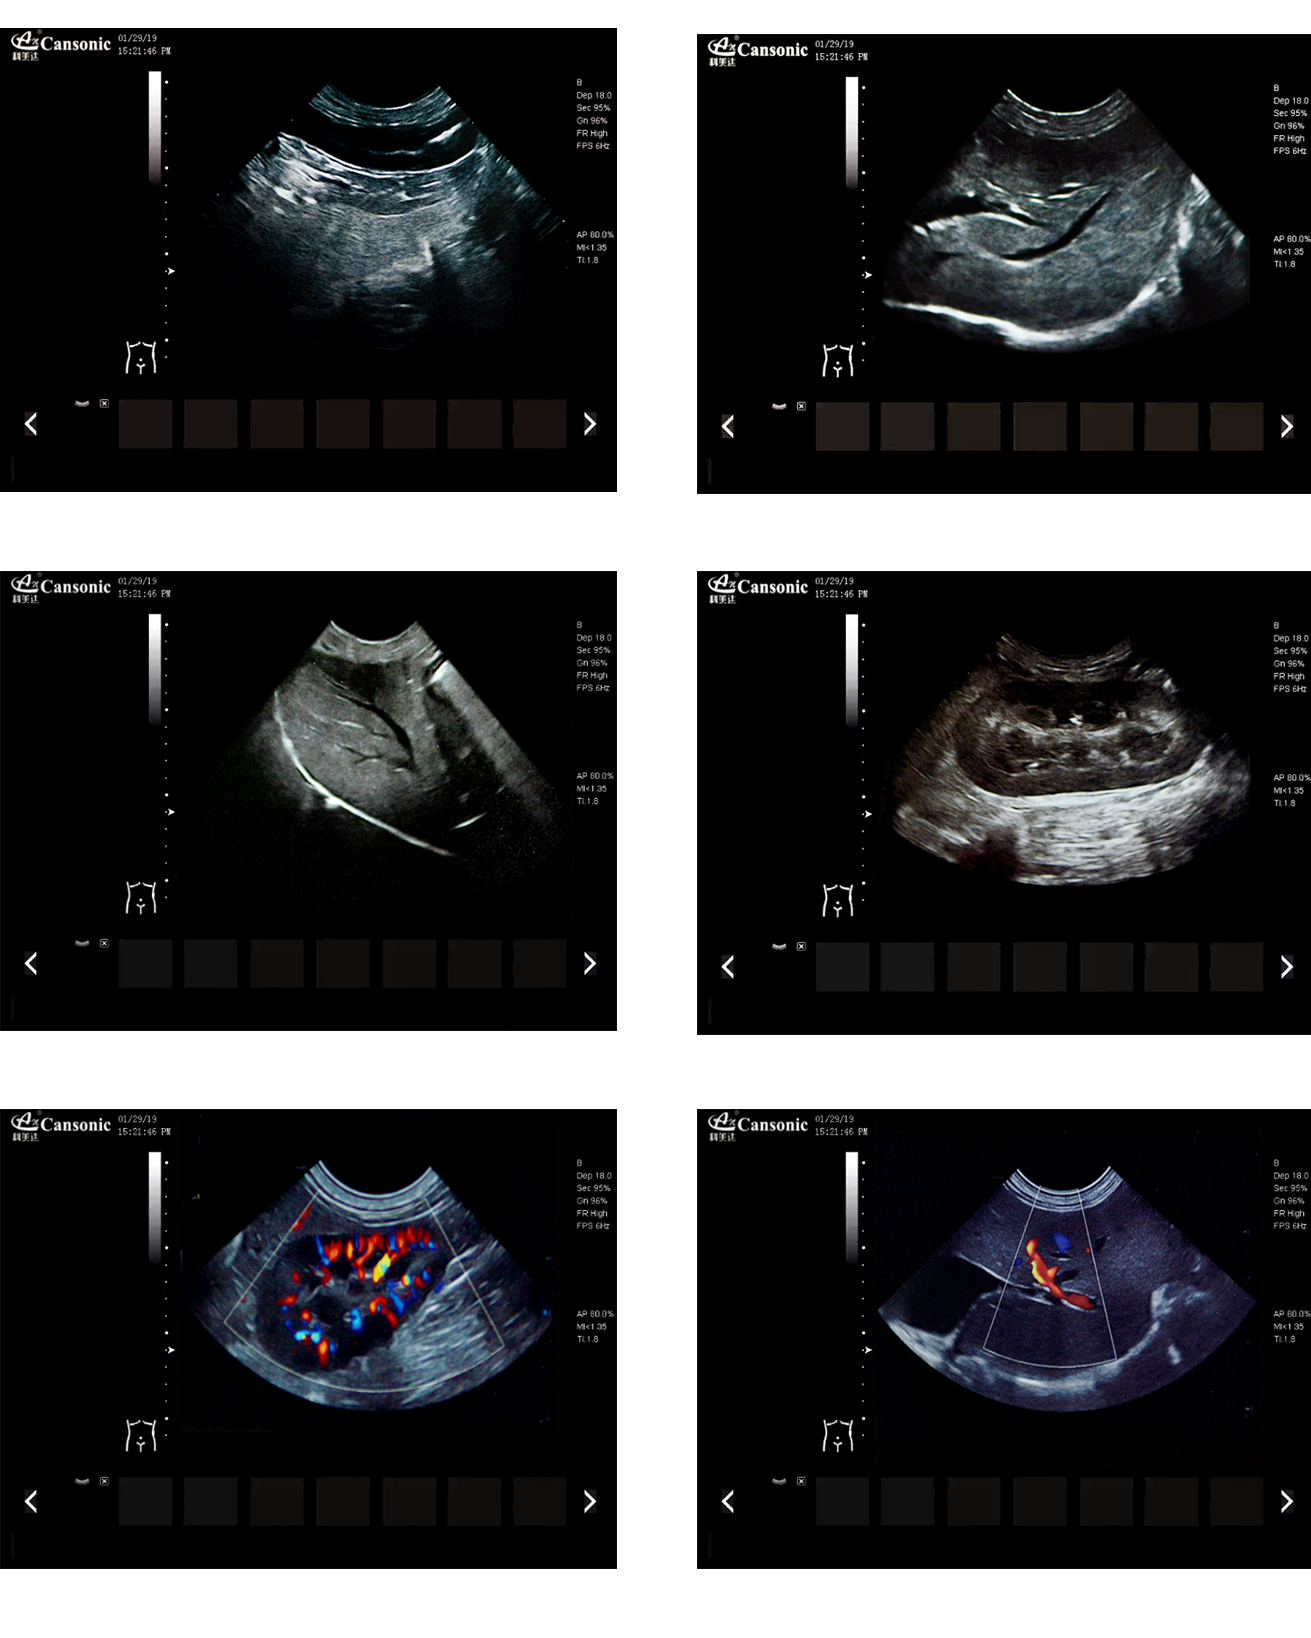

臨床圖示

1、薈萃前沿成像技術,實現高精與靈便的完美融合,提供完整的動物彩超診療方案

2、專業的獸用測量軟件,簡捷的工作流,適合犬、貓、馬、牛、羊等 各類大小動物

3、iClear斑點噪聲抑制抑制噪聲干擾,使動物組織結構更清晰

4、具有廣泛的動態范圍,顯示出色的組織均勻性,減少了偽影及噪聲

5、精細血流識別技術,增加了可疑病變更多的信息分析

6、先進的算法帶來清晰的穿刺針顯示,降低穿刺活檢操作難度